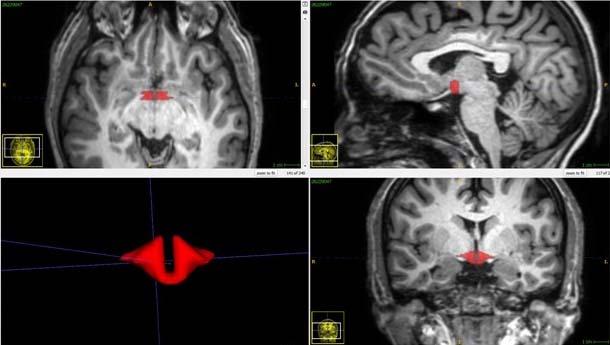

image: Brain MRI depicting hypothalamus in red.

Located at the base of the brain above the pituitary gland, the hypothalamus produces hormones and helps regulate essential bodily functions including body temperature, mood, appetite, sex drive, sleep cycles and heart rate.

In his study, Dr. Lipton and colleagues recruited a group of 50 healthy women, including 21 women who were taking oral contraceptives. All 50 women underwent brain MRI, and a validated approach was used to measure hypothalamic volume.